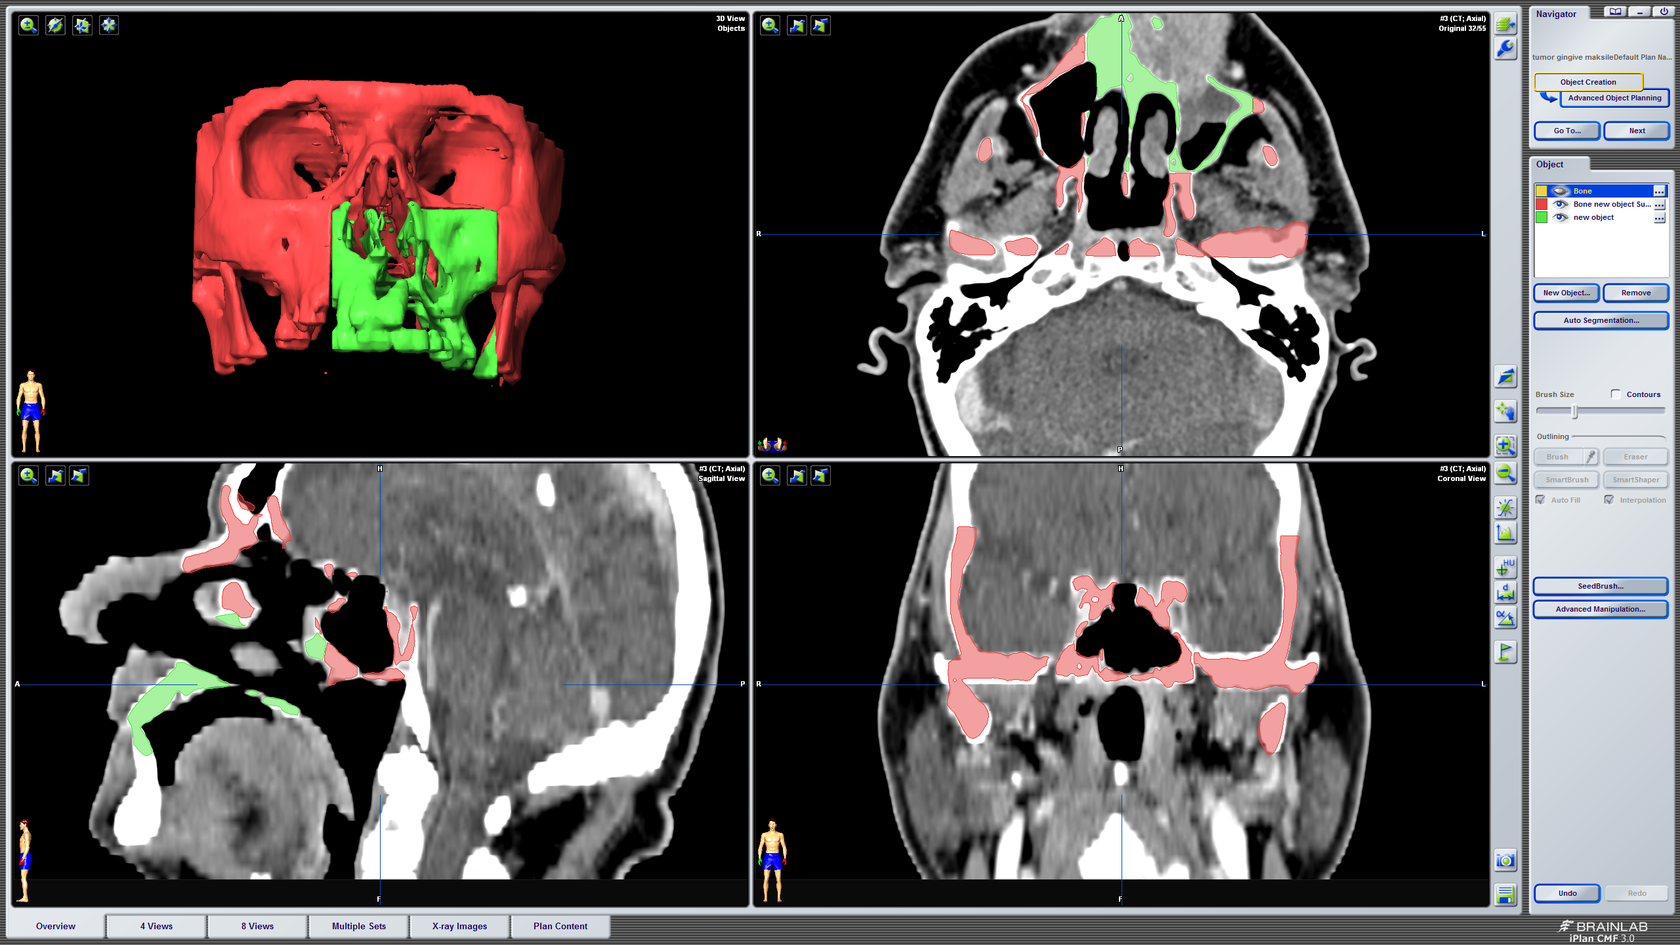

3D kompjutorsko planiranje rekonstrukcije defekta gornje čeljusti